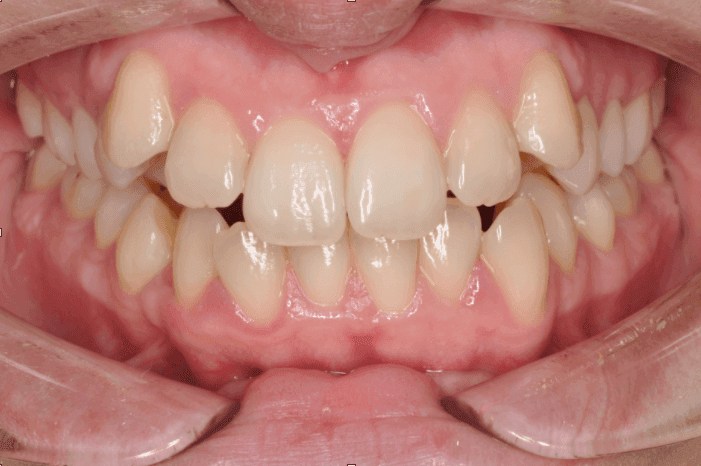

Kako slike obično govore više od reči, na sledećim slikama možete pogledati sjajne rezultate postignute nošenjem fiksnih proteza kod jednog našeg pacijenta: